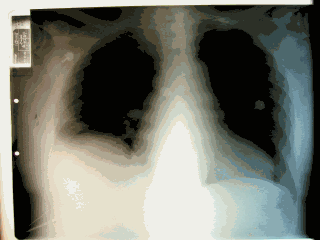

A sample chest X-ray of the patient with pulmonary with CTEPH before and after PTE.

A chest x-ray will usually show hilar fullness attributable to the engorgement of the central pulmonary arteries, clear lung fields, and right ventricular enlargement.